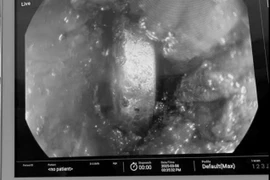

Các bác sĩ tại Bệnh viện Nhân dân Gia Định vừa thực hiện thành công ca nội soi, gắp dị vật vỏ thuốc cho người bệnh D.H.L, 18 tuổi, ngụ tại quận Bình Thạnh, TP HCM. Người bệnh cần thận trọng khi uống thuốc để tránh nhập viện cấp cứu.